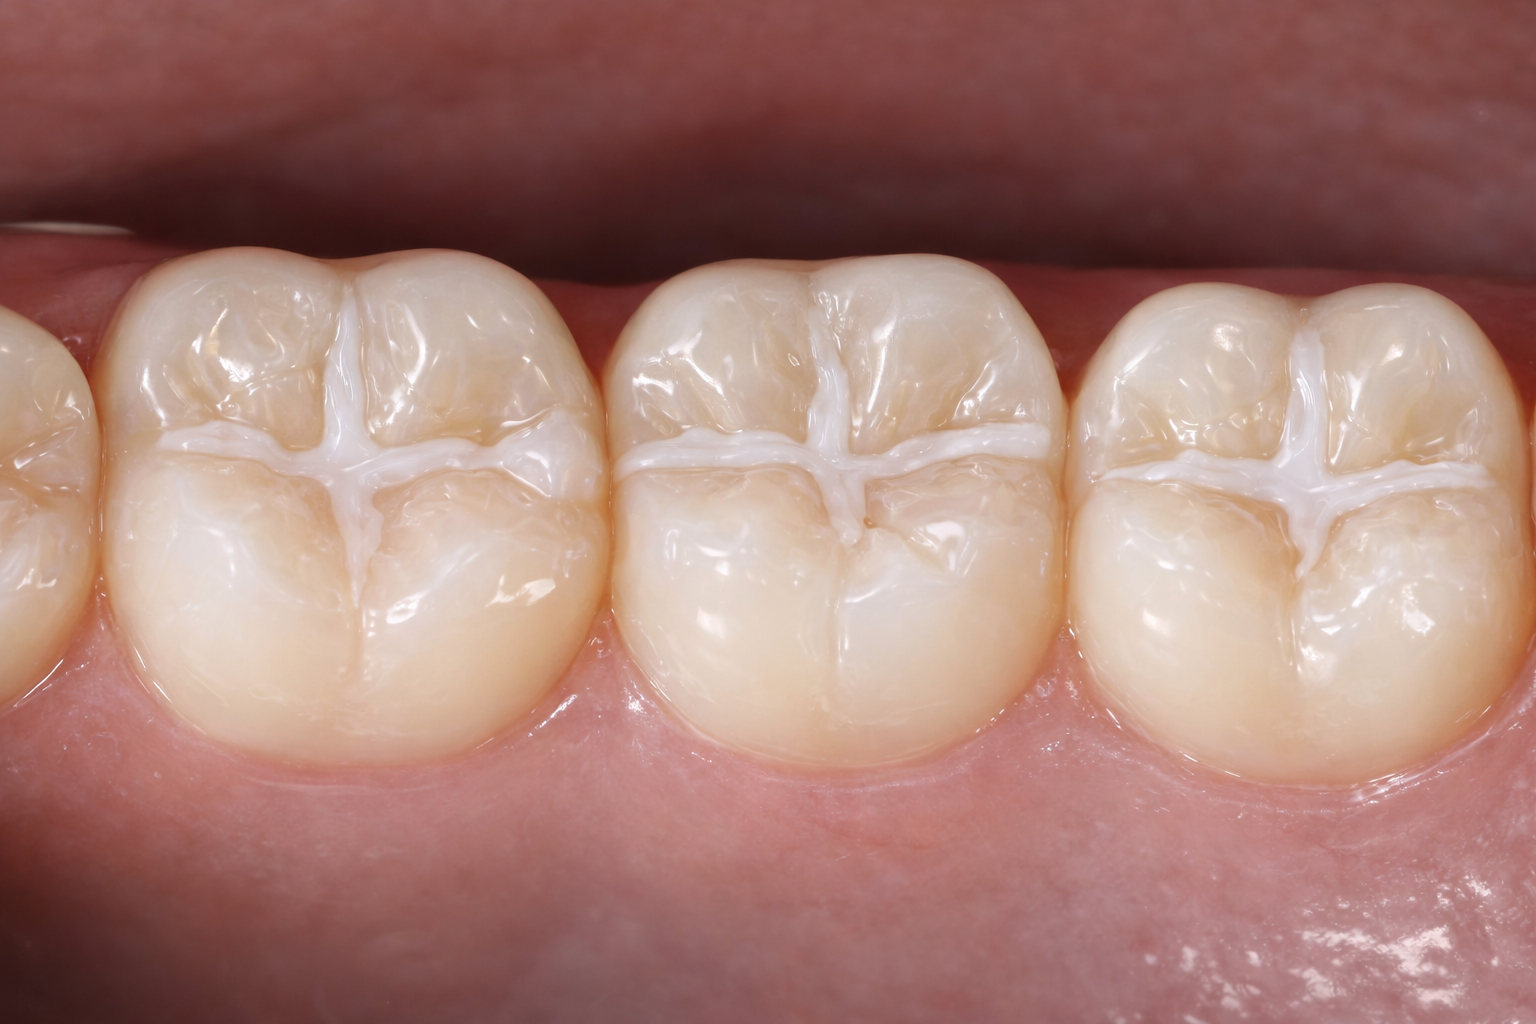

Peptide treatment for tooth decay

Imagine treating tooth decay with medication instead of a filling.